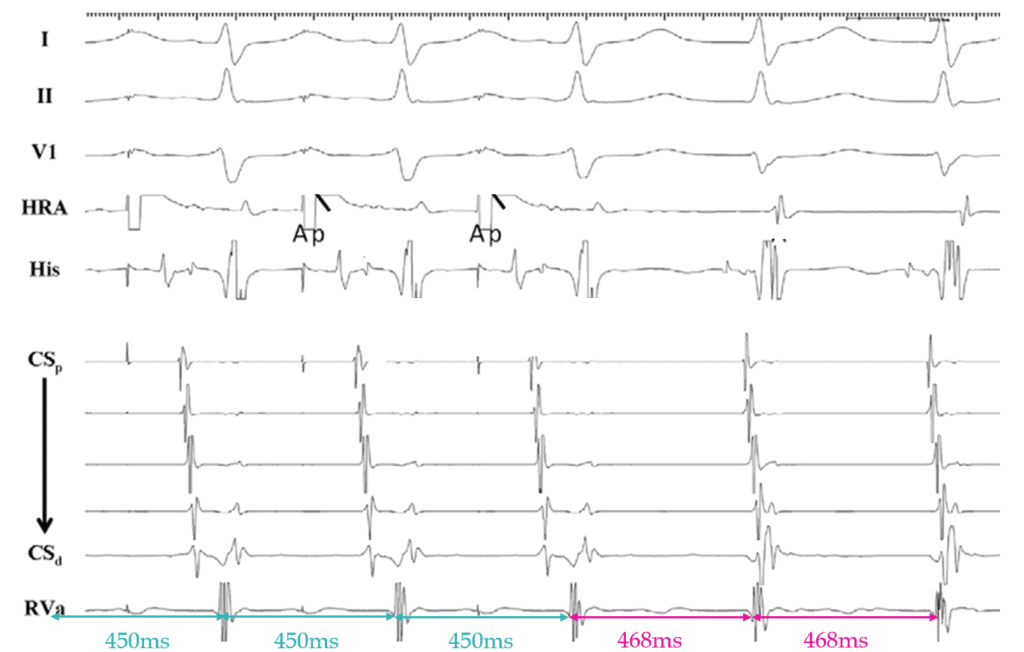

This EGM was obtained from a 46 year old female with presumed AVJRT. After many ablations in the slow pathway region, tachycardia could still be induced, arousing suspicion that perhaps this SVT was not typical AVJRT. Following this, atrial overdrive pacing was performed during tachycardia. What does the below result indicate?

(figure based on: Fan R et al. Novel use of atrial overdrive pacing to differentiate junctional tachycardia from AVNRT. Heart Rhythm. 2011;8(6):840–4)

Answer: This EGM is diagnostic of a focal arrhythmia arising from the His Bundle/AV node due to an AHHA response following successful atrial overdrive pacing, consistent with Junctional Ectopic Tachycardia.

Pacing the atrium 20ms faster the the TCL is useful in differentiating JET from AVJRT in patients with 1:1 AV conduction.

You must accelerate tachycardia to your pacing cycle length and the tachycardia must continue at it’s original TCL.

1. An AHHA response is diagnostic for JET.

2. An AHAH response indicates Reentry (AVJRT/AVRT).

Top tip: Always confirm your last entrained His/V signal! Measure it, don’t assume it.